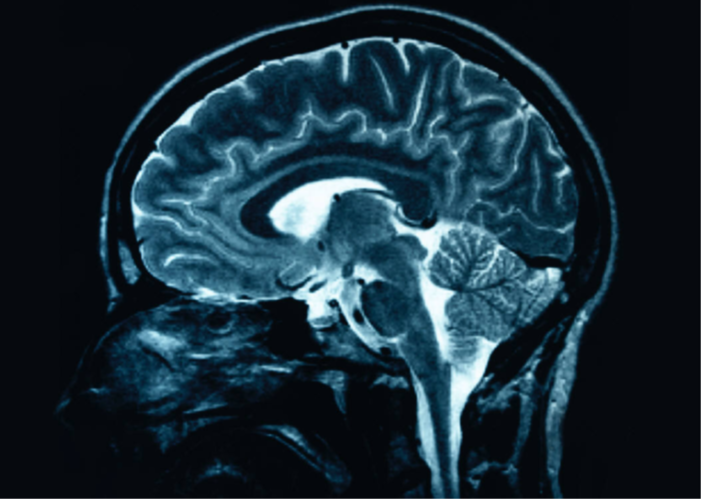

图片

•MRI是一种用于可视化内部、详细介绍身体结构的成像技术。MRI可以创建更详细的、比X射线更清晰的人体图像。

•此程序使用磁场和脉冲或无线电波拍摄体内器官和结构的照片。我们体内的水是由数百万个原子组成的,当置于磁场中时,这些原子与场对齐,就像指南针指向北极一样。